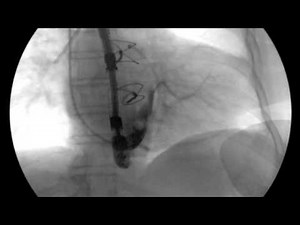

Your Cardiac Catheterization at th…

YouTubeMichigan Medicine